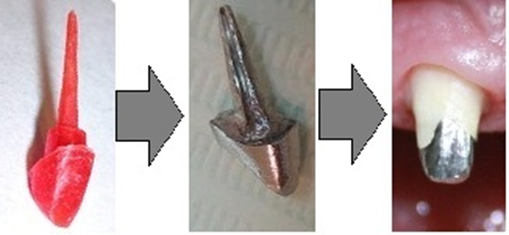

Культя зуба это

Культя зуба это 106 фото